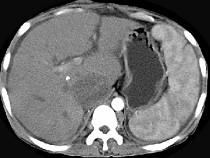

问题 女性,26岁,腹胀不适7月,腹软,肝右肋缘下1cm,影像检查如图,可能的诊断为 ( )

选项 A.肝血管瘤 B.原发性肝癌 C.肝硬化腹水 D.巴-希综合征 E.脂肪肝

答案 D